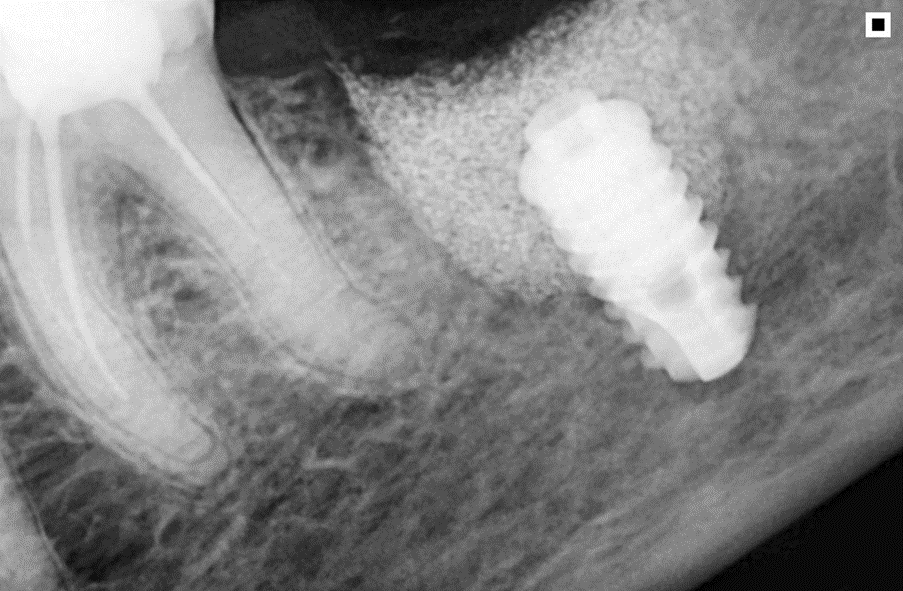

O Extra Graft é um biomaterial muito interessante para aplicação nestes casos, pois apresenta-se na forma de blocos fracionados (0,5g / 1g / 2g) e tem em sua composição 75% de hidroxiapatita (principal componente mineral do osso) e 25% de colágeno do tipo I (proteína mais abundante na porção orgânica do osso) – ambos de origem bovina. Devido a essa composição, possui grande atividade osteocondutora e maior adesão dos osteoblastos, aumentando a velocidade de neoformação óssea. Além disso, a porção de colágeno gera maior estabilidade do coágulo e ação hemostática, promovendo menor sangramento pós operatório e maior conforto ao paciente. O Extra Grafté de fácil manuseio e condensação dentro dos alvéolos e é radiopaco, facilitando a conferência do preenchimento via radiografia final do procedimento.

A sequência de imagens a seguir apresenta casos da aplicação clínica do Extra Graft em cirurgias de exodontia e implante imediato com preenchimento dos gaps, e apenas exodontia e preenchimento alveolar para favorecer a regeneração óssea.